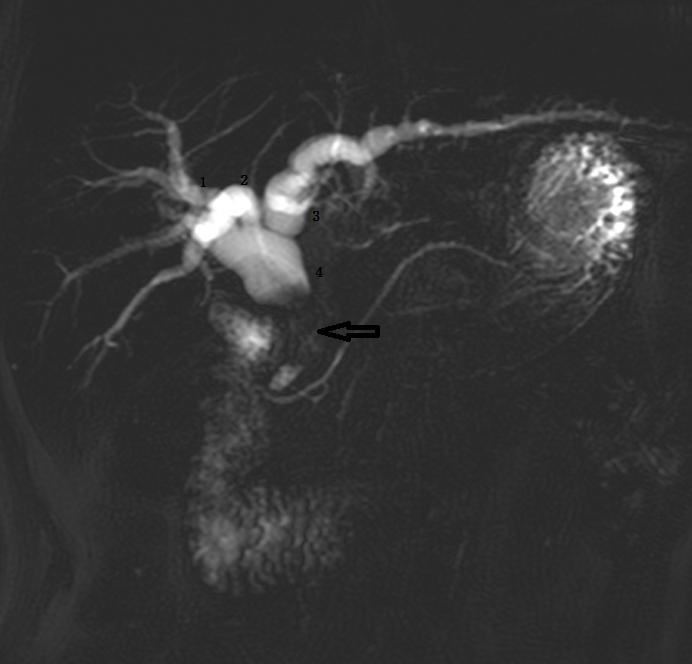

Ⅲa 型:右后肝管汇入左肝管。左图:1 为右前肝管,2 为右后肝管,3 为肝左管,4 为肝总管,5 为胆总管。

Ⅲb 型为右后肝管汇入肝总管。图 1 为右前肝管,2 为肝左管,3 为右后肝管,4 肝总管,5 胆囊管,6 胆总管。